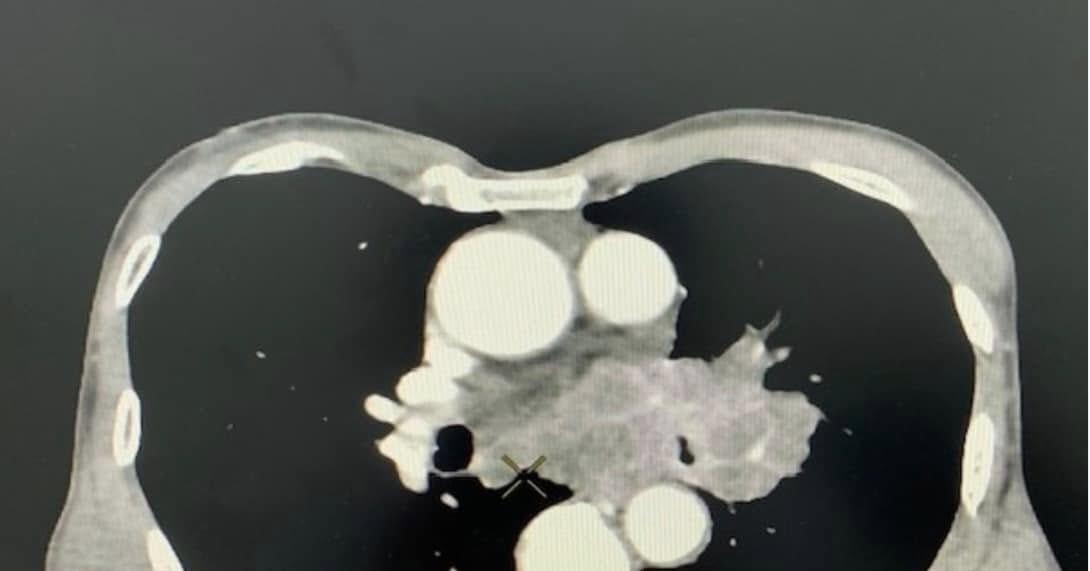

Kết quả chụp cắt lớp vi tính lồng ngực cho thấy bệnh nhân có khối u vùng trung thất và rốn phổi trái, bờ không đều, ngấm thuốc ở thành khối và vào các vách bên trong. Tổn thương hướng tới u phổi, dạng u phế quản trung tâm, xâm lấn trung thất, gây hẹp phế quản gốc trái. Sau khi có kết quả, ông N. đã được chuyển đến bệnh viện chuyên khoa để điều trị tiếp.